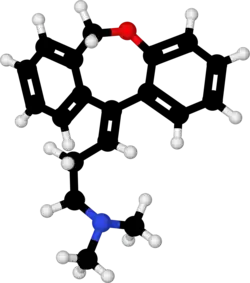

| Formula | C19H21NO |

| Molar mass | 279.383 g·mol−1 |

Chemistry

Doxepin is a tricyclic compound, specifically a dibenzoxepin, and possesses three rings fused together with a side chain attached in its chemical structure.[48] It is the only TCA with a dibenzoxepin ring system to have been marketed.[72] Doxepin is a tertiary amine TCA, with its side chain-demethylated metabolite nordoxepin being a secondary amine.[50][51] Other tertiary amine TCAs include amitriptyline, imipramine, clomipramine, dosulepin (dothiepin), and trimipramine.[73][74] Doxepin is a mixture of (E) and (Z) stereoisomers (the latter being known as cidoxepin or cis-doxepin) and is used commercially in a ratio of approximately 85:15.[2][75] The chemical name of doxepin is (E/Z)-3-(dibenzo[b,e]oxepin-11(6H)-ylidene)-N,N-dimethylpropan-1-amine[48][76] and its free base form has a chemical formula of C19H21NO with a molecular weight of 279.376 g/mol.[76] The drug is used commercially almost exclusively as the hydrochloride salt; the free base has been used rarely.[2][77] The CAS Registry Number of the free base is 1668-19-5 and of the hydrochloride is 1229-29-4.[2][77]